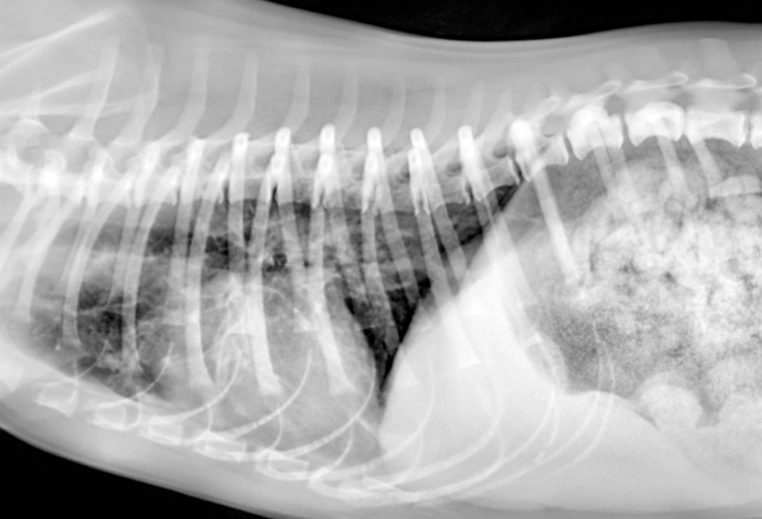

第二步:影像學檢查——胸腔X光。 這是診斷肺積水的黃金標準。在X光片上,正常的肺部是黑色的(充滿空氣),積水的肺部會出現白色、雲霧狀的區域。獸醫可以從分布位置(是瀰漫性還是局部?)初步判斷原因。